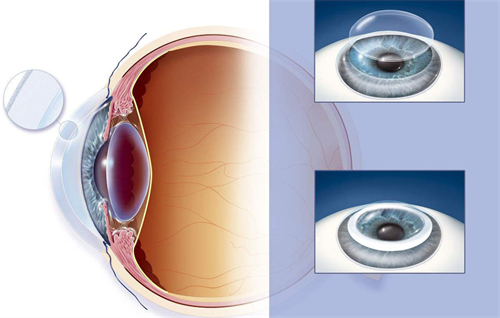

进口人工晶体常采用疏水性丙烯酸酯、硅胶等高端材料。

这些材料不仅生物相容性更优,还能降低后囊混浊风险,延长晶体使用寿命。

例如,美国爱尔康的PanOptix三焦点晶体,可同时满足远、中、近视力需求,适合需要频繁切换用眼场景的患者;瑞士ICL的胶原共聚物晶体,厚度仅50微米,植入后无异物感,尤其适合角膜偏薄的高度近视人群。

此外,进口晶体还提供“可调节型”“景深延长型”等创新设计,为复杂病例提供更多选择。